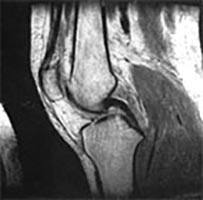

O exame clínico pode identificar a lesão do ligamento cruzado posterior, pois existem testes específicos para avaliar este ligamento. Complementarmente, o exame de ressonância magnética permite melhor documentação desta lesão.